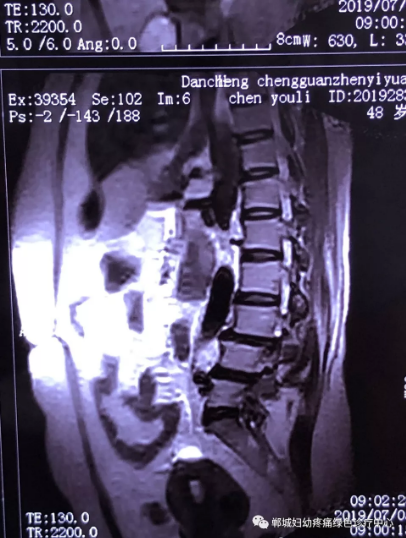

2年前,雙樓鄉(xiāng)的陳女士不小心摔了一跤后出現(xiàn)腰痛,當(dāng)時到藥店買了膏藥來貼,疼痛減輕了一些,但是從此以后反反復(fù)復(fù)出現(xiàn)腰痛。到處進(jìn)行治療,不見好轉(zhuǎn),最近腰痛加重了,痛得受不了,出現(xiàn)行走后甚至持續(xù)的雙下肢后側(cè)或后外側(cè)放射性的疼痛麻木、間歇性跛行等癥狀。陳女士趕忙去醫(yī)院治療,做了磁共振檢查后確診為腰椎滑脫、腰椎反弓。醫(yī)生都告訴她需要手術(shù)治療。隨后她又帶著片子咨詢了好幾家醫(yī)院,結(jié)果都是一樣,她已經(jīng)做好了手術(shù)的打算。

治療前